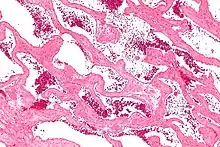

Cavernous hemangioma

Micrograph of a cavernous liver hemangioma. H&E stain.